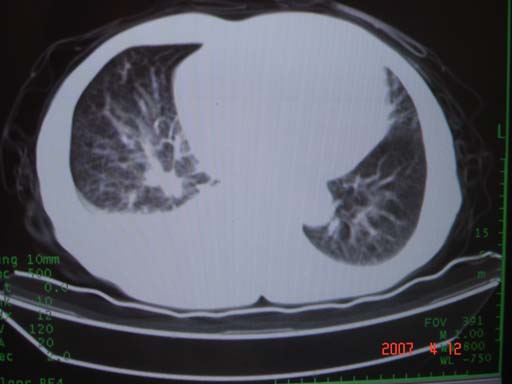

帮我 看看。男77岁咳嗽咯血2月发热2周!病人一般情况可 口痰为鲜红,有点象洗肉水(我看见他吐的痰了)

病灶局限在右肺中上叶,呈大片状实变影,内见空气支气管征,支气管分支较柔软,纵隔内未见肿大淋巴结.支持:感染性病变_1 大叶性肺炎.2 干酪性肺炎.

优先考虑右上肺干酪性肺炎并同侧中叶播散、胸腔积液。分析:右膈肌未见升高、纵隔未见明显右移,胸部各组淋巴结未见可疑肿大,中叶可见支气管铸形,肺野、肺门未见可确定肿块。

支持右侧大叶性肺炎、右侧胸腔积液。建议严格抗炎治疗后复查或支气管镜检进一步检查。

右肺上叶中心型肺癌并上叶阻塞性肺炎,中叶炎症,右侧胸腔积液

右肺上叶后段支气管中断,首先考虑中央型肺癌并右肺不张及纵隔淋巴结转移,右侧胸腔积液。

右肺中心型肺癌可见支气管呈鼠尾状

考虑右侧中央型肺癌伴中上肺阻塞性肺炎、不张,淋巴结肿大,胸腔积液。,建议支纤镜检查

有点象洗肉水的痰,其来源应当是实变引起的血细胞渗出导致,可见支气管气象,实变区有虫蚀状空洞,有明显胸腔积液,未见明显肺门区肿块影,考虑继发型肺结核,干酪性肺炎